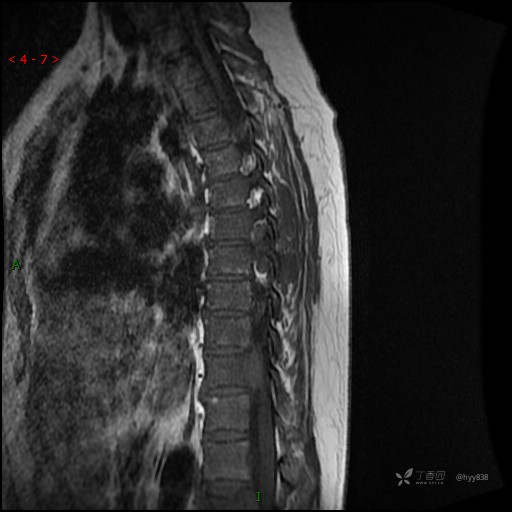

MRI SAG T2WI+T1WI